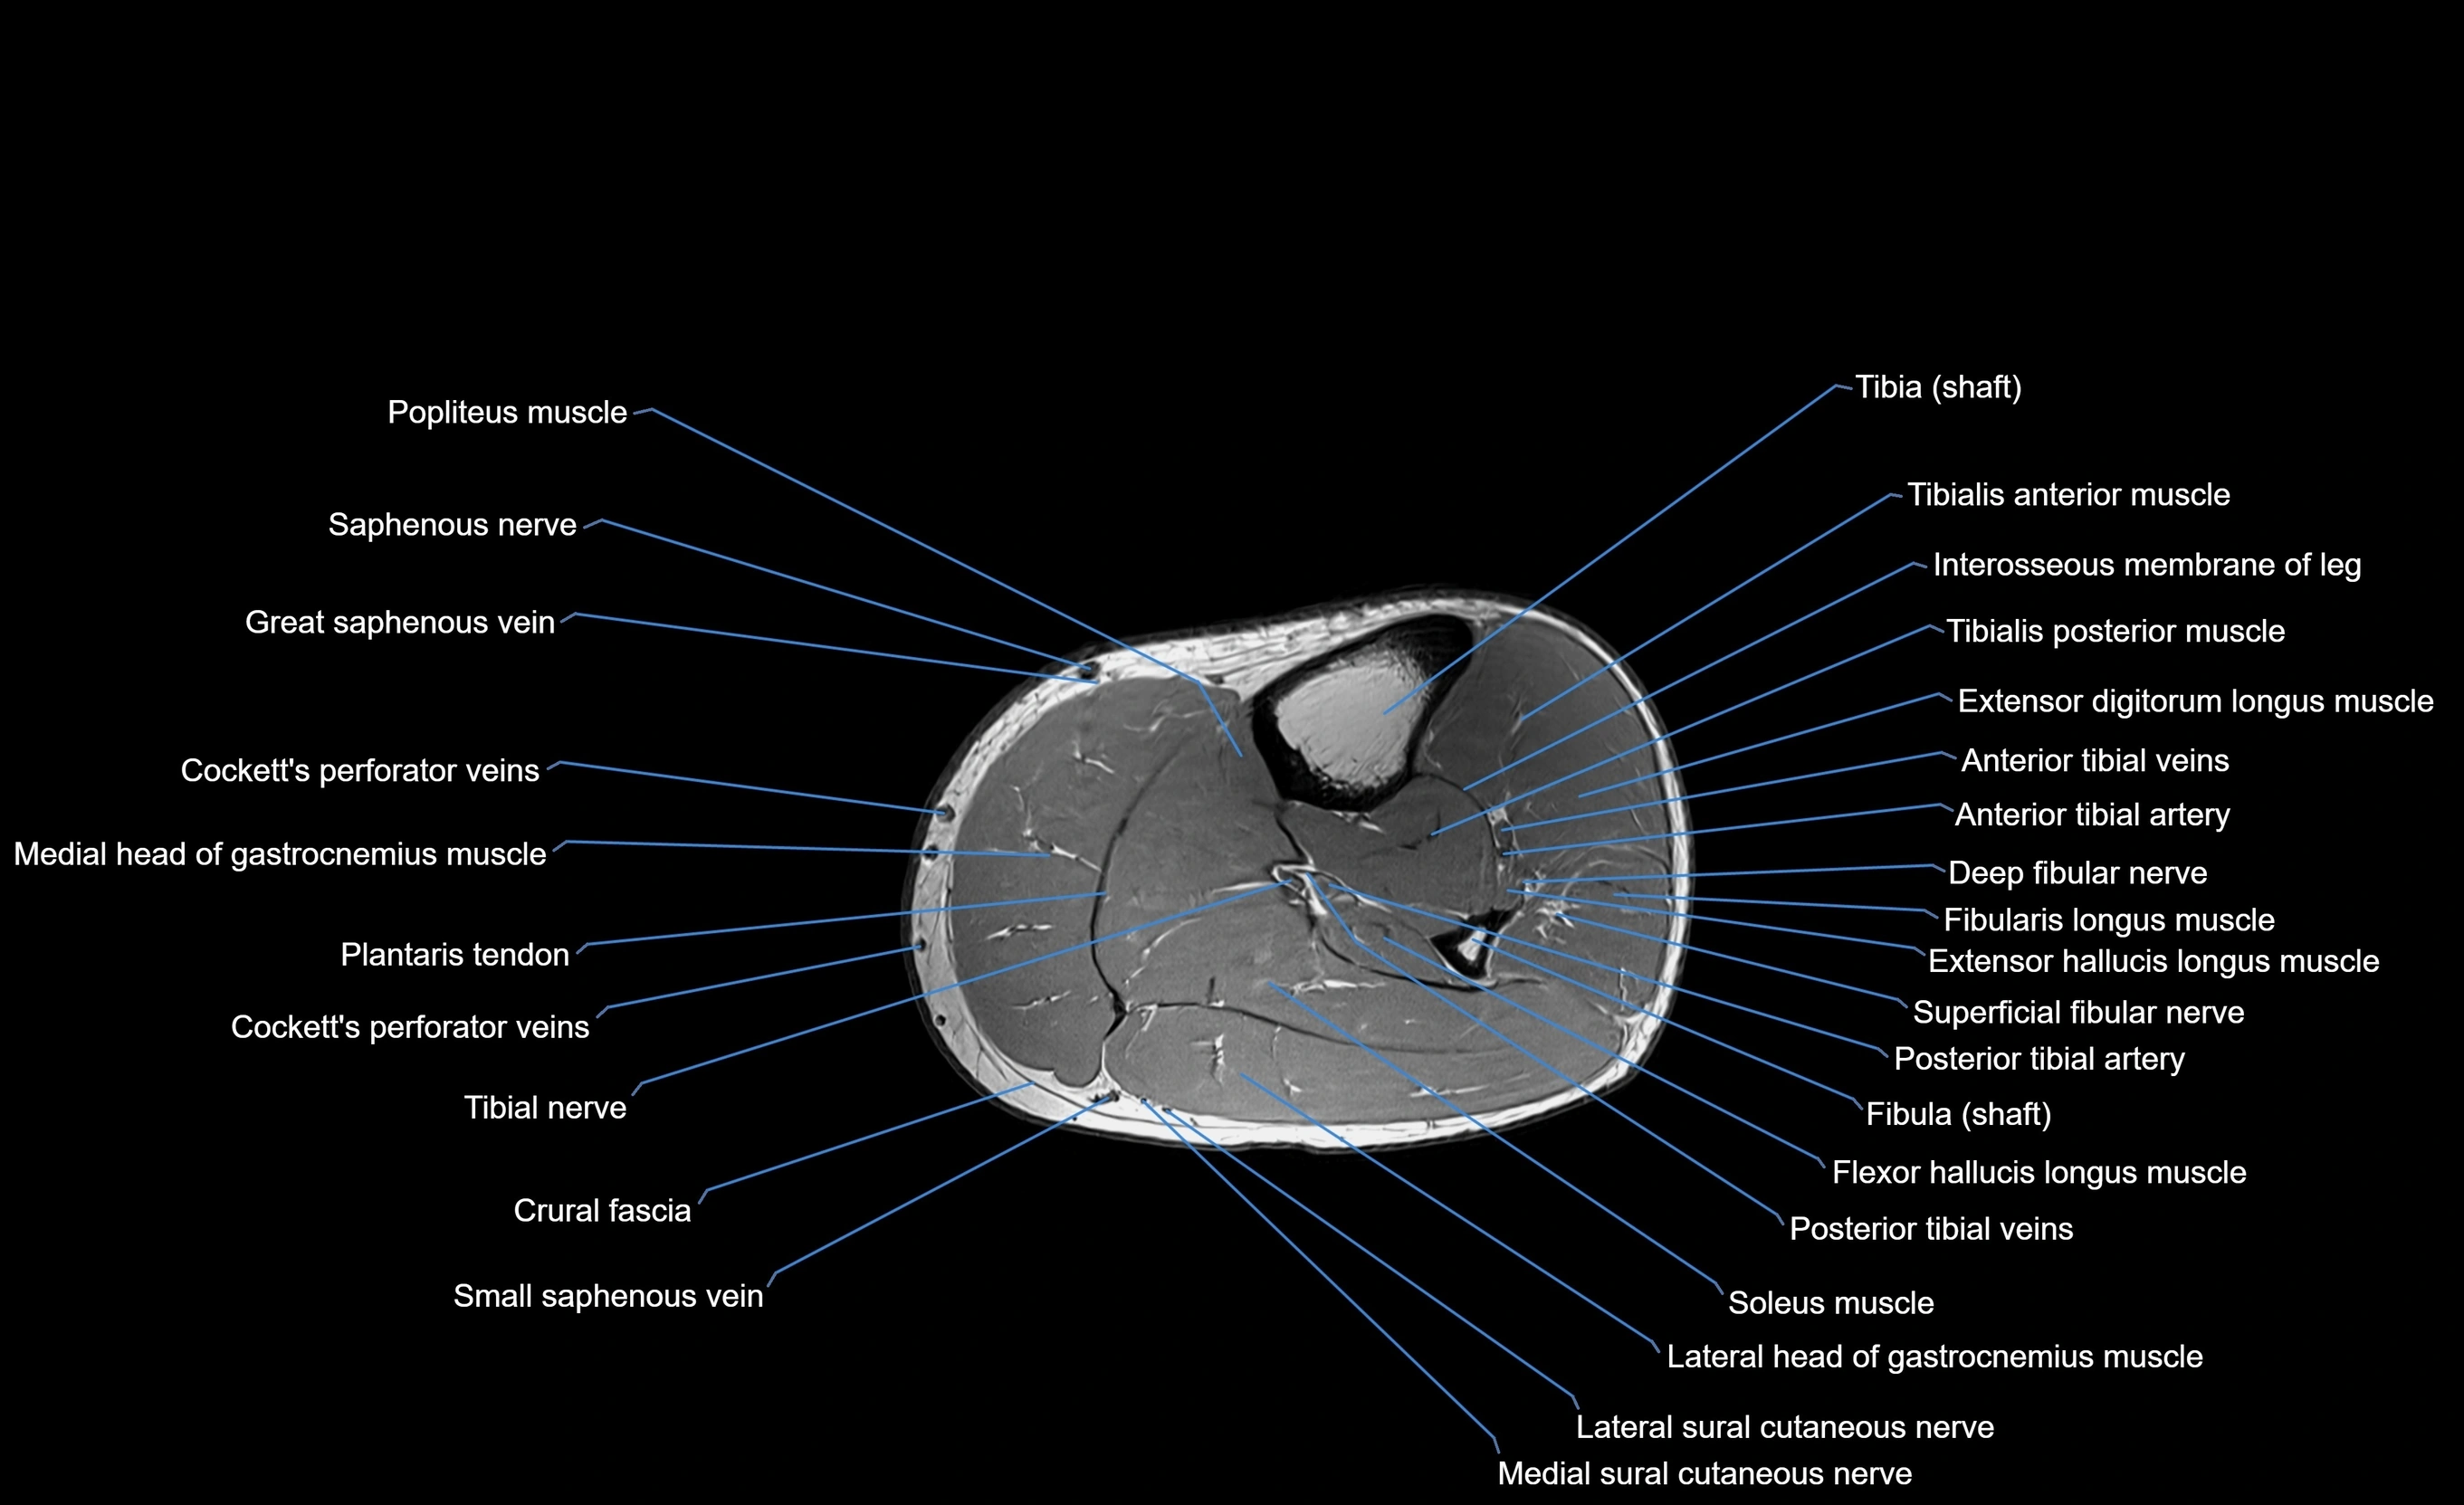

MRI image